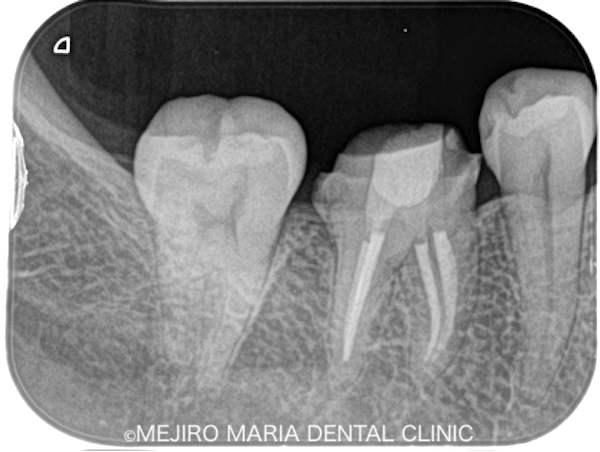

|治療詳細画像_4-1.png)

|治療詳細画像5.png)

クラックトゥースの原因歯を特定できた場合、治療の選択肢は下記の2つです。

① 歯髄を保存したまま全部被覆冠(※)を装着する。

② 神経を除去した後、全部被覆冠を装着する。

※全部被覆冠:歯冠全体を覆う被せ物

① の場合、神経は残すことができますが、将来的にクラックが進行した際、歯髄炎に罹患し、強い痛みが出る可能性があります。

② の場合、神経を取ることになりますが、クラックが進行しても歯髄炎を回避することができます。

将来的にクラックがどのくらいのペースで進行していくか、もしくは完全に歯の破折を予防できるかは不透明なため、この選択は重要であると考えます。

今回の患者様は、精密根管治療を行うことで、治療の成功率が比較的高いうちに処置を完了させる②の治療を選択されました。精密根管治療は必要最低限の歯質削除量で治療が完了することから、有意義な選択と言えます。